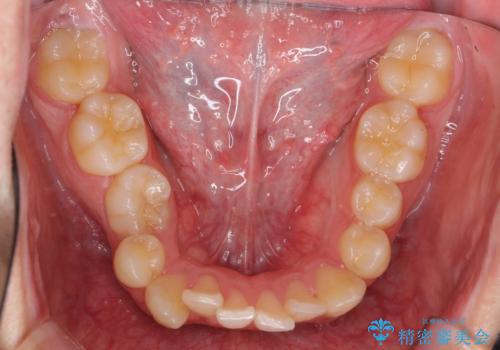

すきっ歯・出っ歯が気になる インビザライン矯正 乳歯をインプラントに

- 前歯の並びをきにして来院。

歯を抜かずに、やすりがけすることでスペースを獲得し、前歯をしっかり下げました。

また、インビザラインに先駆けて、右下はワイヤーによる部分矯正を行い、犬歯をしっかり後ろに下げました。

下げる時に、矯正用ミニスクリューを使用しています。